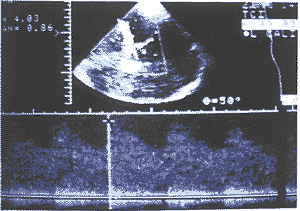

1.17例烟雾病患者的CDE和DSA检查结果:在17例烟雾病患者的102条大脑主要动脉中 ,CDE 显示49条血管闭塞,(ACA 27条、MCA 20条、PCA2条),而DSA显示51条完全闭塞(ACA 23条、 MCA 22条、PCA 6条),二者诊断相符者44条(ACA 23条、MCA 19条、PCA 2条)。CDE显示15条 血管狭窄,其中血流明显降低者12条(ACA 1条、MCA 5条、PCA 6条),血流明显升高者3条( 均为MCA),而DSA诊断为狭窄者12条(ACA 4条、MCA 6条、PCA 2条),二者诊断相符者8条(AC A 1条、MCA 5条、PCA 2条),如图1、2。CDE显示38条血管正常(ACA 6条、MCA 6条、PCA 2 6条),而DSA显示39条正常(ACA 7条、MCA 6条、PCA 26条),有1条ACA,DSA显示正常而CDE 未发现血流 信号。102条血管中,有7条CDE显示为低速血流信号者(MCA 3条、PCA 4条),DSA显示为完全 闭塞。有4条CDE显示为完全闭塞者(ACA 3条、MCA 1条),DSA显示为狭窄。

图2 多普勒示同一患者左侧MCA起始

段可测及4.03m/s的高速血流